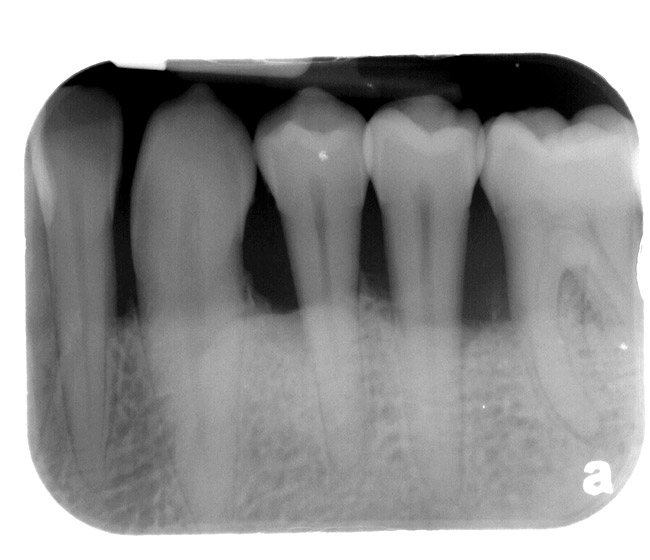

Figure 8  CLINICAL GUIDELINES  Horizontal defects can make guided tissue-regeneration attempts unpredictable.

Figure 8

Figure 9  CLINICAL GUIDELINES Narrow vertical defects respond more favorably to regeneration attempts. If periodontal surgery is attempted in the anterior region, the possibility of an esthetic compromise should always be considered regardless of defect morphology.

Figure 9

Bone defect morphology plays an important role in the predictability of tooth retention as well. Horizontal defects are unpredictable to guided tissue regeneration attempts (Figure 8). Narrow vertical defects respond more favorably to regeneration attempts (Figure 9).21